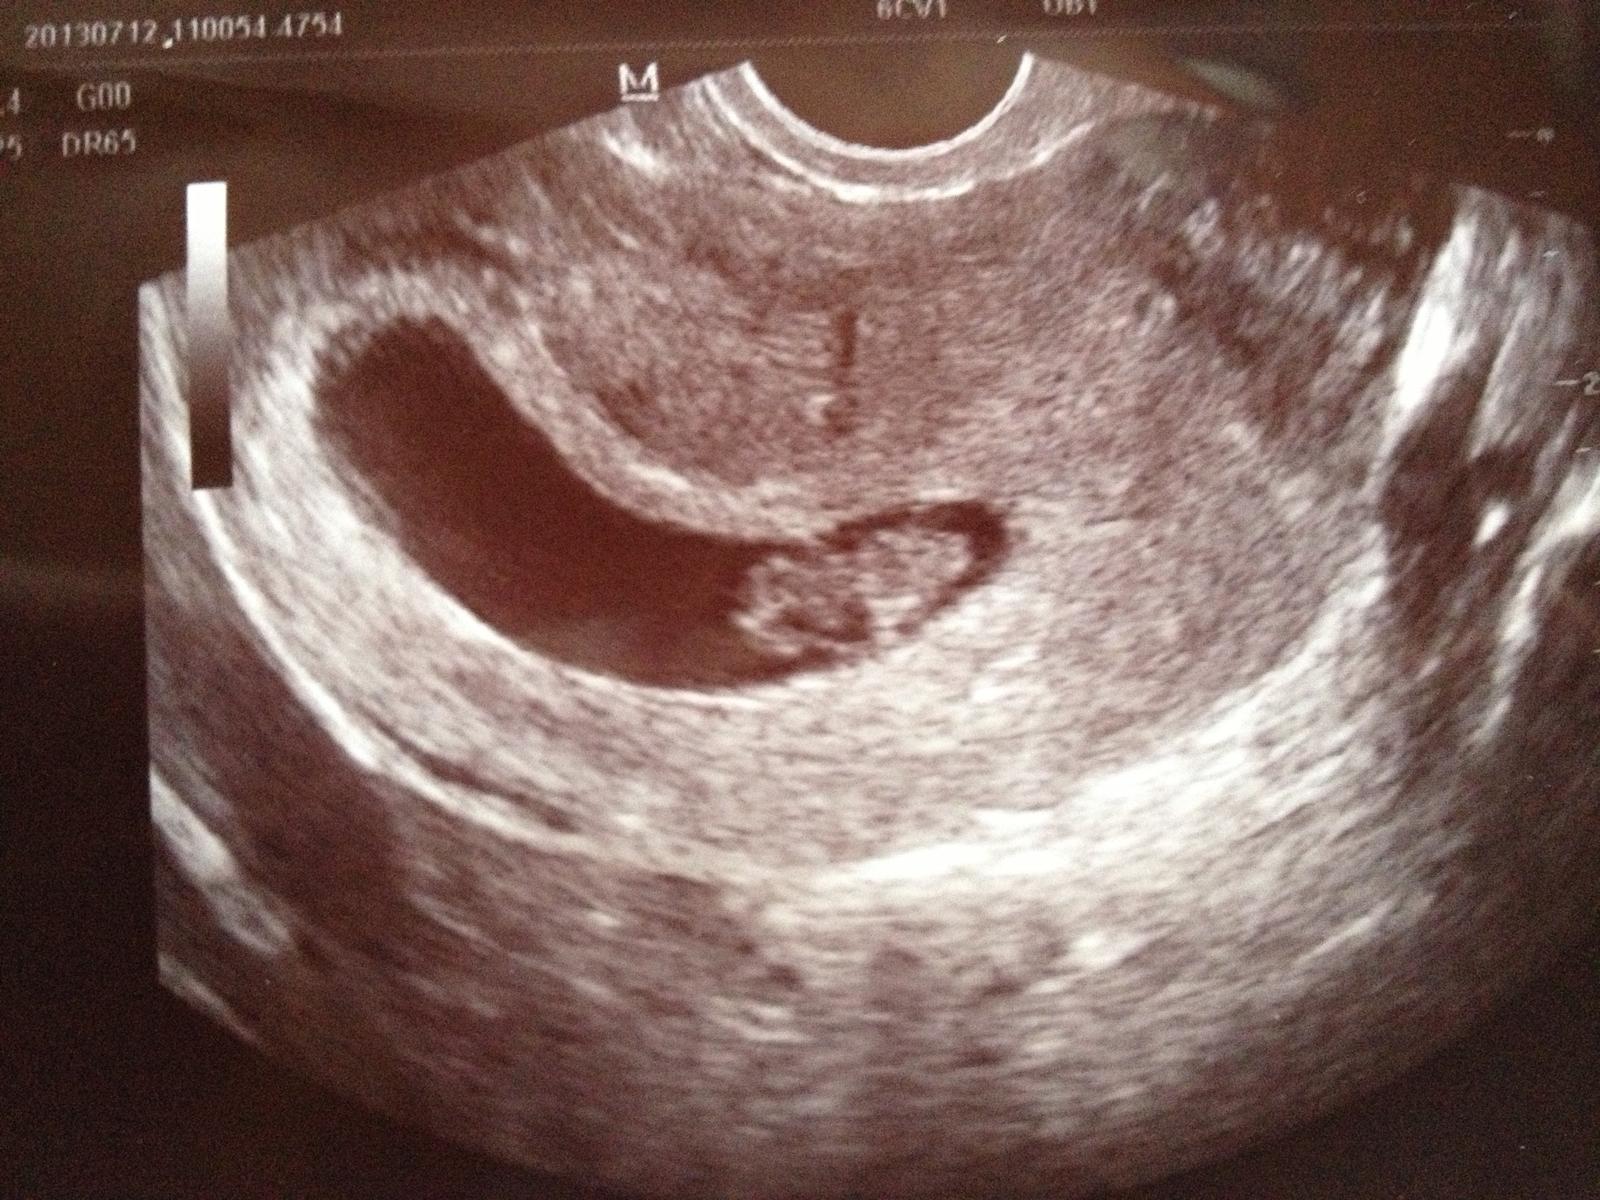

Ahojte Februarovky, potichucky sa k Vam aj ja pridavam🙂 som v 8. tyzdni, TP mam az koncom februara. srdiecko vcera bilo o106, velmi sa tesime! Mame uz doma 15mes nezbednika, tak to bude vesele 🙂 verim, ze vsetko dotiahneme v zdravi do uspesneho konca a vo februari/marci budeme drzat nase uzlicky v naruci!